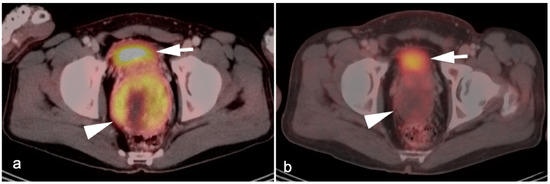

10. Anal Carcinoma